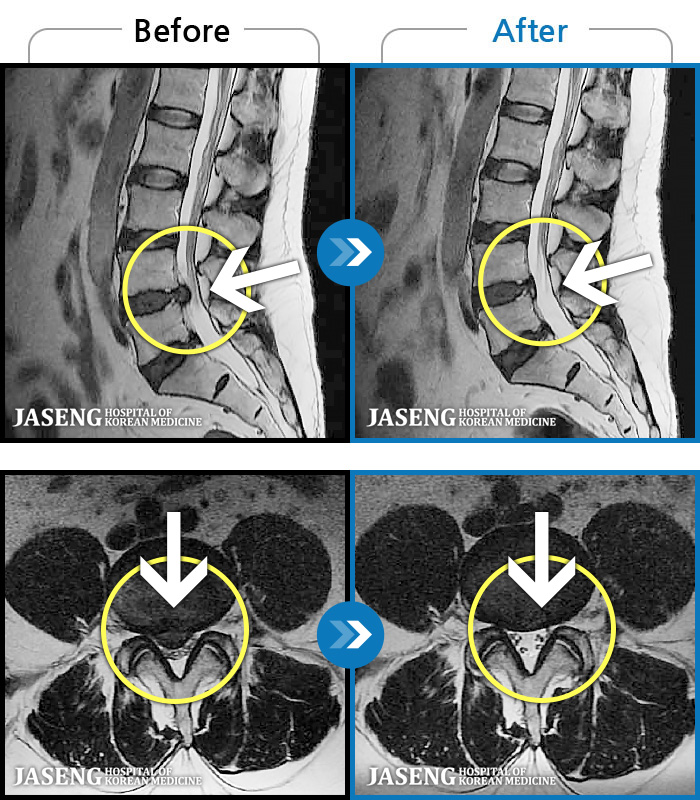

MRI ġ

1,237 MRI ũ ʸ Ȯϼ.